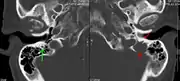

A CT of the brain revealed a lytic lesion in the left temporal bone (right side of image), and petrous temporal bones involving the mastoid segment of the facial nerve canal. Red arrows: lesion; green arrow: normal contralateral facial nerve canal. The lesions are consistent with a myeloma deposit.

The diagnostic examination of a person with suspected multiple myeloma typically includes a skeletal survey. This is a series of X-rays of the skull, axial skeleton, and proximal long bones. Myeloma activity sometimes appears as "lytic lesions" (with local disappearance of normal bone due to resorption). And on the skull X-ray as "punched-out lesions" (pepper-pot skull). Lesions may also be sclerotic, which is seen as radiodense.[47] Overall, the radiodensity of myeloma is between −30 and 120 Hounsfield units (HU).[48] Magnetic resonance imaging is more sensitive than simple X-rays in the detection of lytic lesions, and may supersede a skeletal survey, especially when vertebral disease is suspected. Occasionally, a CT scan is performed to measure the size of soft-tissue plasmacytomas. Bone scans are typically not of any additional value in the workup of people with myeloma (no new bone formation; lytic lesions not well visualized on bone scan).